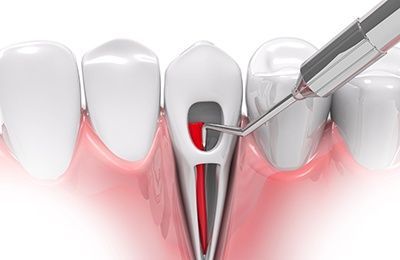

How We Do a Root Canal

Our root canals are quick and painless. Dr. Elbialy ensures you are adequately anesthetized and comfortable before beginning the procedure. He uses an electronic apex locator and NiTi instruments for speed, pinpoint precision, and accuracy.